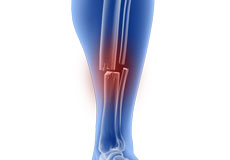

Tibia Fractures in Children

Fractures of the tibia, also called the shinbone, are a common injury in children. A crack or break in the tibia is referred to as a tibial fracture. Most breaks usually occur in the middle of the tibia or “tibial shaft”, known as a tibial shaft fracture.